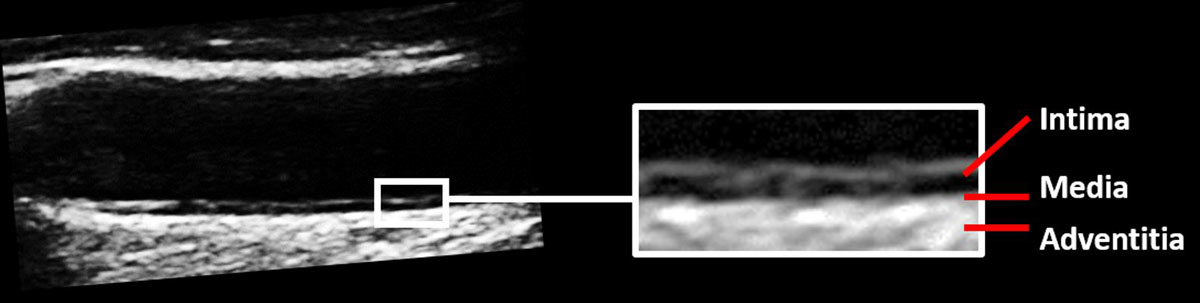

Carotid ultrasound is performed with a linear array probe (fig. 1) with a high frequency of at least 7 MHz in order to obtain sufficient resolution to image small structures [11]. The image resolution depends on the depth and the frequency used [12, 13] and is usually around 0.3 mm [14]. The anatomical region of interest is the tunica intima, which is assessed with 2D imaging without Doppler. Intima-media thickness (IMT) is the distance between the endothelium and the tunica adventitia (fig. 2). According to the Mannheim consensus, IMT is preferably measured in the far wall segment of the last 10 mm of the common carotid artery [15] (fig. 3). One major problem with carotid IMT measurements lies in the diversity of methods used, as described extensively elsewhere [16]. The variability of carotid IMT measurements is lowest in the far wall of the common carotid artery with the exclusion of carotid plaque (figs 3 and 4 ), but this increase in reproducibility goes with a loss in prediction of cardiovascular events [20, 21].

Figure 2 Anatomy of the carotid artery wall. The image represents the far wall of the common carotid artery showing the intima and media, defined by the distance between the endothelium and the external elastic membrane. For clinical purposes, the distance between the endothelium and the tunica adventitia is measured to obtain the intima-media thickness (IMT).